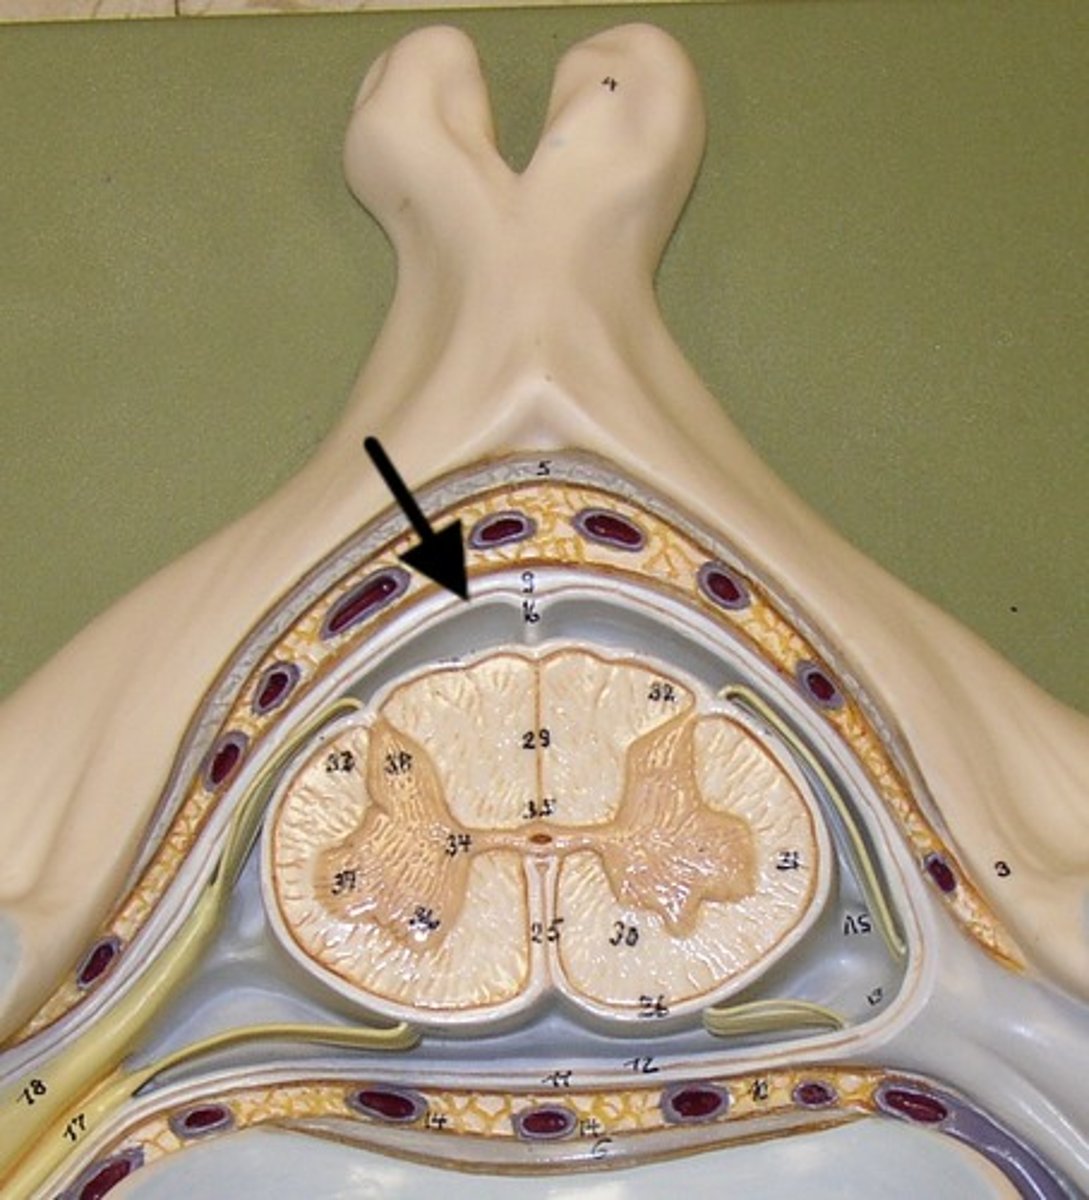

posterior median sulcus

anterior median fissure

Name this groove

epidural space

dura mater

subdural space

arachnoid mater

subarachnoid space

pia mater